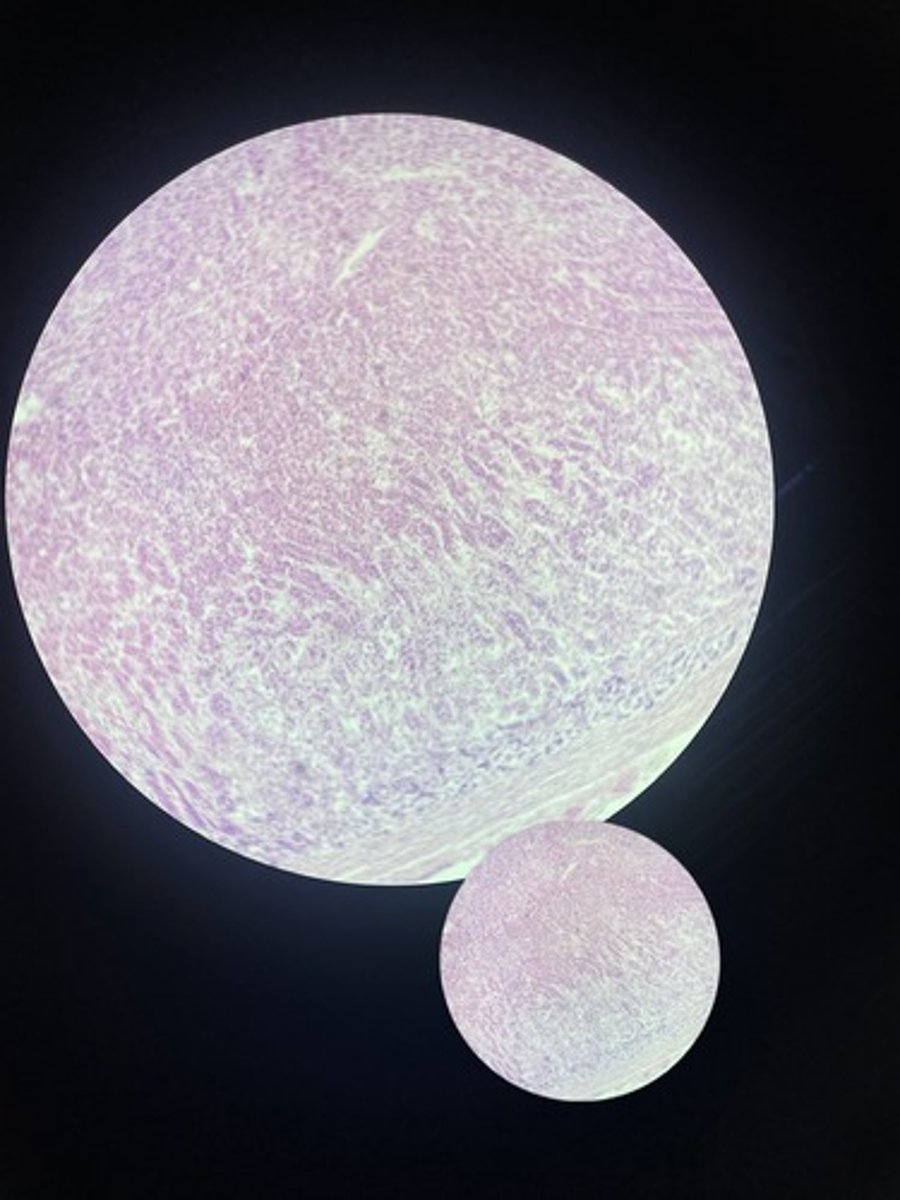

Adrenal gland HE

Adrenal gland HE

Adrenal gland HE

Adrenal gland HE

Adrenal gland